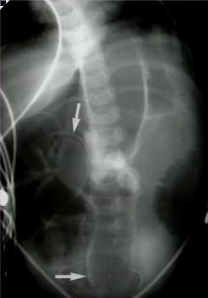

What does this patient have?

Ascities. Note increased density, central bowel loops, thickened peritoneal fat stripe, loss of other edges (liver, spleen and bladder)

What causes this?

Pneumoperitoneum can be caused by rupture of a hollow viscous from cancer, infection, infarction, surgery…